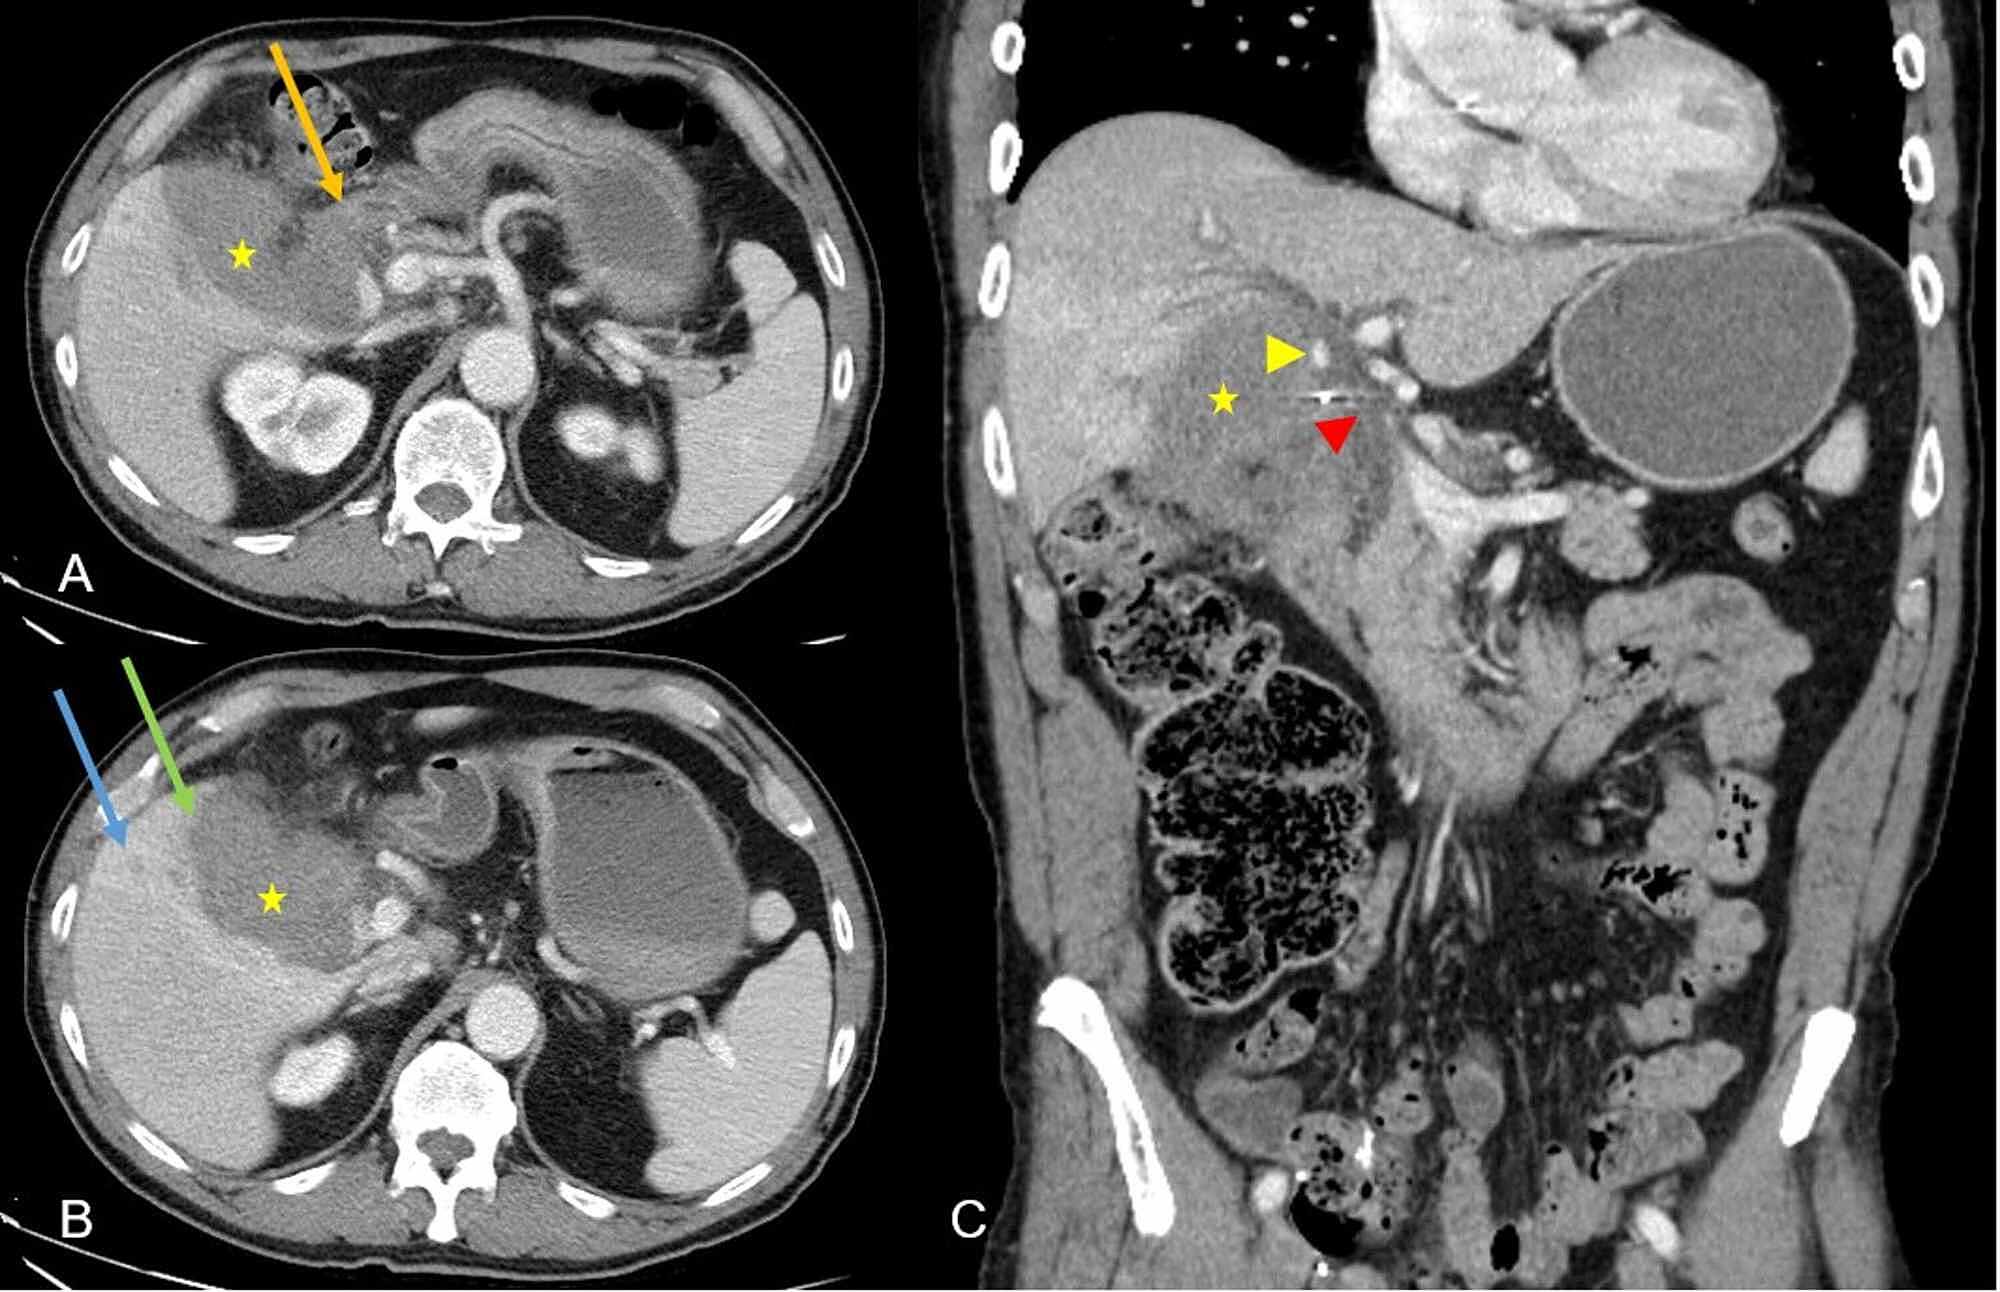

Multi Modality Imaging Features Distinguish Pancreatic Carcinoma

Multi Modality Imaging Features Distinguish Pancreatic Carcinoma

Multi Modality Imaging Features Distinguish Pancreatic Carcinoma